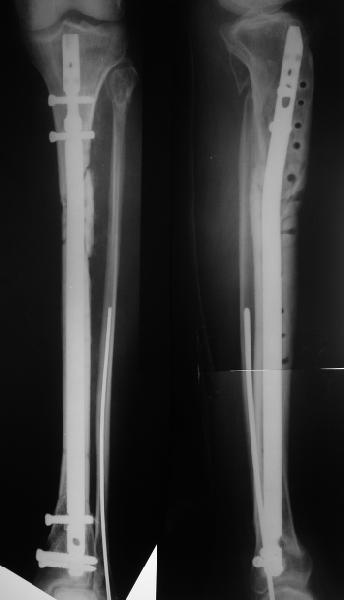

Alexander Chelnokov 26 Июнь 2004, 01:07

Декабрь 2003

22 июня 2004

Еще раз спасибо! Сделали вчера. Все прошло по плану, интраоперационное фото после удаления пластинки и итоговые снимки прилагаю. Гвоздь бесканальный 12 мм. Сегодня пациентка уже ходит по палате с одним костылем.